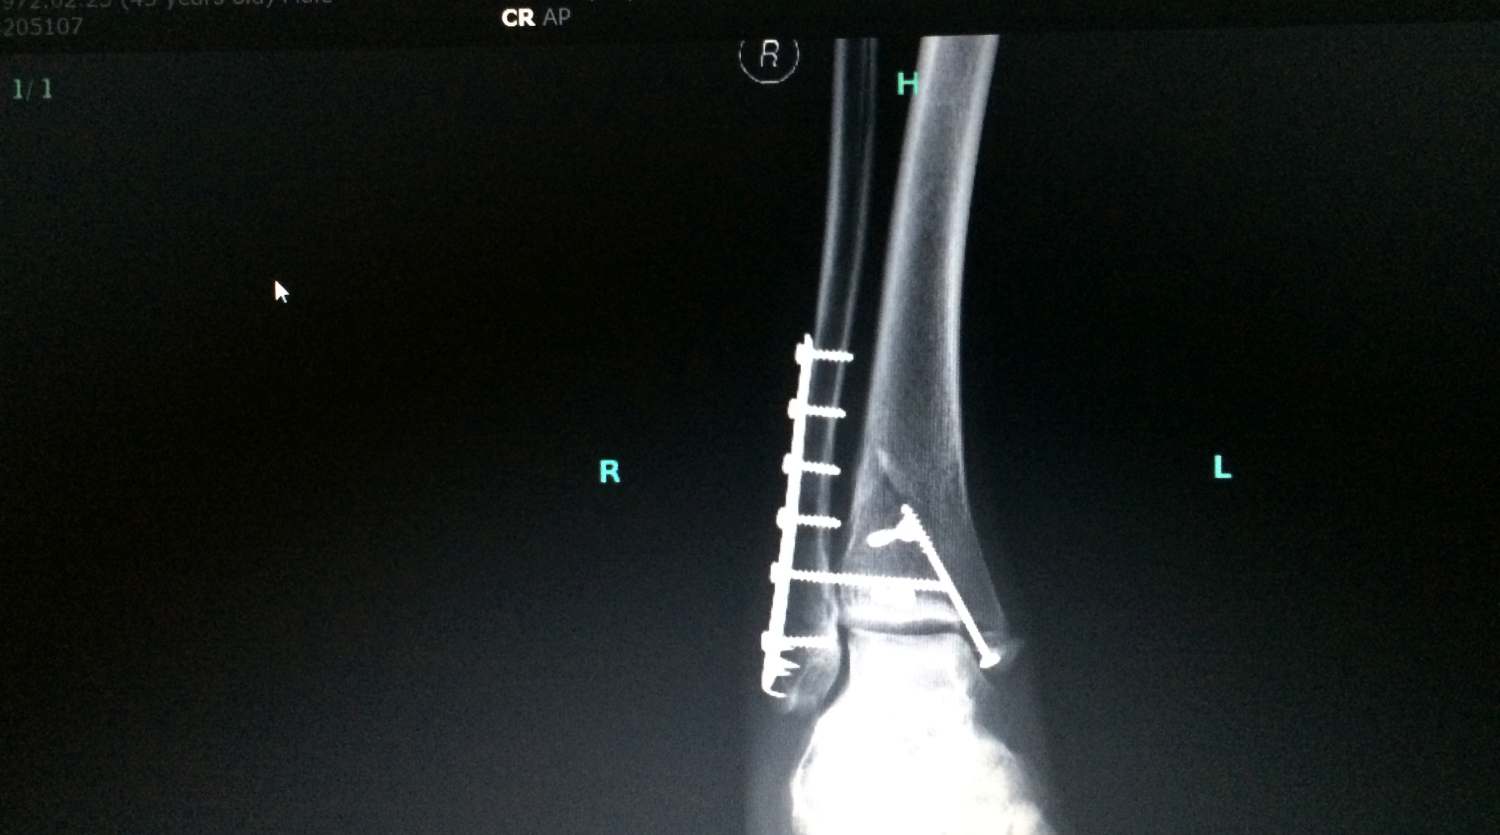

Innen már „futószalagon” zajlott a kezelés: a Szent János Kórház Ortopéd Traumatológiáján landoltunk, ami koránt sem hasonlít egy négycsillagos wellness-szállodára, de – és ez sokkal fontosabb – az ott dolgozók hozzáállása és szaktudása feledtette a hiányosságokat! Kiderült, a baleset során keletkezett háromszoros bokatörést műtéti úton kell helyreállítani, karmos lemezeléssel és csavarozással. A műtétet dr. Juhász András végezte, aki maga is motorozik. A profizmusa mellett az emberi oldaláról is nagyon pozitív benyomást tett ránk: bátorította, jó tanácsokkal látta el Zolit, emellett nagyon együtt érző volt, és a humora is kiváló – ezúton is hálával tartozunk neki.